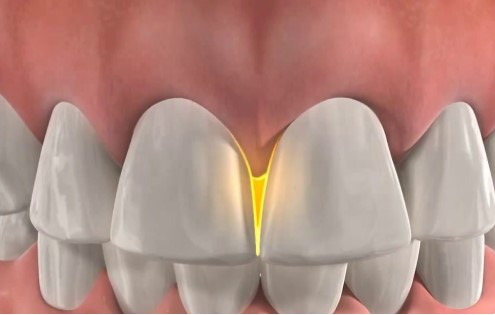

치간공극(블랙 트라이앵글)을 줄이기 위해

또 하나 중요한 이유는 바로 치간공극(Black Triangle, 블랙 트라이앵글) 문제입니다.

치간공극이란

치아와 치아 사이를 채워야 할 잇몸(유두)이 위로 올라가거나 줄어들면서

치아 사이가 검게 비어 보이는 삼각형 모양의 공간을 말합니다.

요즘은 “블랙 트라이앵글”이라는 용어를 알고 직접 검색해서 오시는 분들도 많습니다.

이때 치간삭제를 시행하고 공간을 다시 닫아 주면서

블랙 트라이앵글이 완전히 사라지지는 않더라도

눈에 띄게 크기가 줄고, 치아 사이가 더 긴밀하게 붙어 보이는 효과를 얻을 수 있습니다.